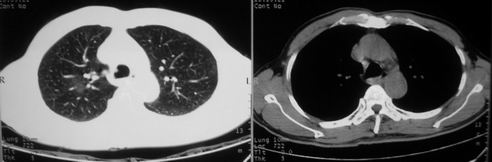

男,62岁,咳血两天。无其他不适。

右肺上叶浅淡密度增高影,考虑炎性病变

像多个结节聚集在一起的病变,且密度较淡  首先考虑为结核吧  建议密切复查

片状磨玻璃影,考虑肺泡出血可能性大,其他不排除,建议hrct

右上磨玻璃样密度影,考虑就是个肺泡出血,别的没有

病灶呈“磨玻璃影”,较薄,周围无卫星灶,很难一口说是肺结核,建议积极治疗后,短期复查!(支持考虑:肺泡出血!)

右肺上叶可见多发磨玻璃状影,符合肺泡内出血表现,严格意义上讲应该是肺泡内积血。引起出血的原因很多,不一定非得结核所致。